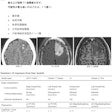

According to the findings, the algorithm perfectly classified the laterality (F1 scores of 100% on the testing set). When classifying the imaging projection, the algorithm achieved F1 scores of 99.2% on anterior-posterior views, 100% on axillary views, and 100% on lateral views.

In addition, when classifying the implant type, the model achieved F1 scores of 100% on preoperative images, 95.2% on aTSA, and 100% on RSA x-rays.